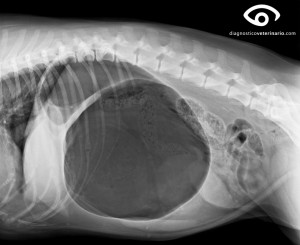

La dilatación del estómago se debe a una gran cantidad de gases, líquidos, o incluso comida, en el interior del estómago del perro. Este gran volumen de sustancias impide que el aparato digestivo se vacíe de forma adecuada.

Es un problema grave que debe tratarse con la máxima urgencia, ya que puede acabar con la vida del perro en cuestión de horas. La atención veterinaria precoz es de vital importancia

Para saber más……….Torsión gástrica